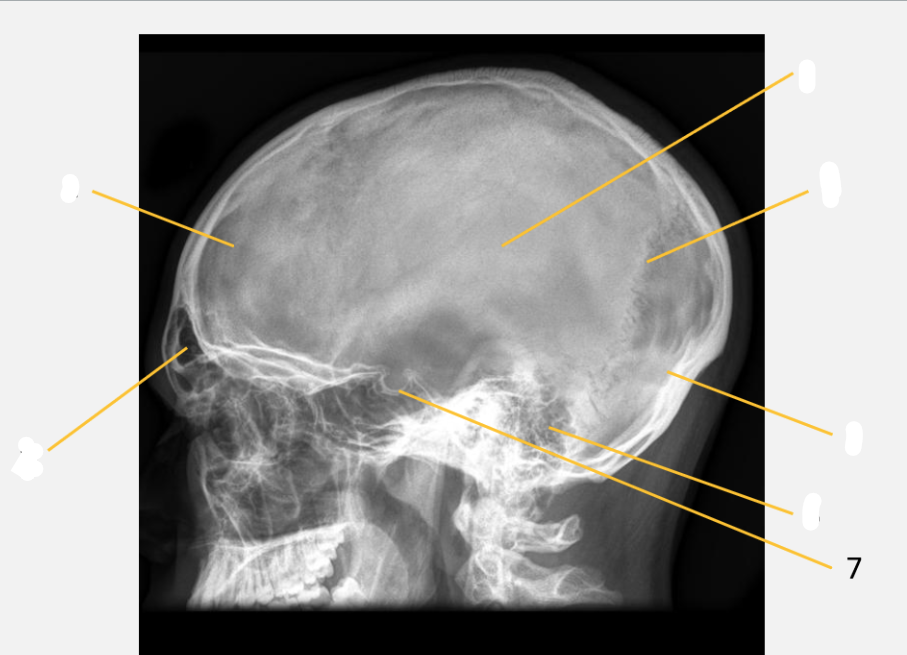

frontal bone

frontal sinus

parietal bone

lambdoid suture

occipital bone

mastoid air cells

Sella turcica